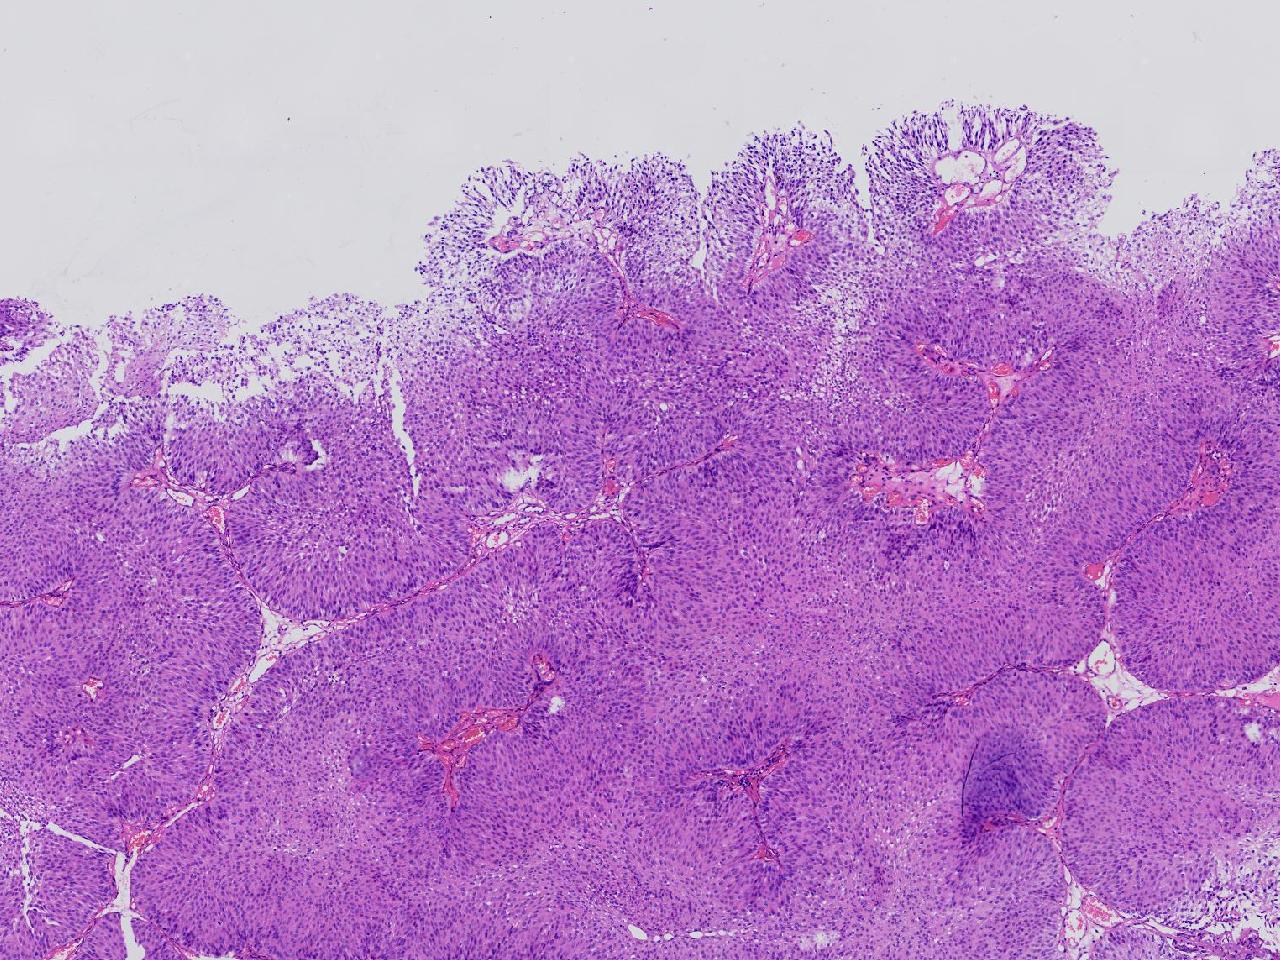

男,79岁,膀胱肿物。

膀胱肿物

灰白色不整形软组织多块,2X1X1厘米。

考虑:乳头状尿路上皮癌

考虑低级别,非浸润。

乳头状尿路上皮癌,低级别。

这几张图片上没有看到明确的浸润。